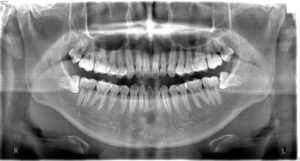

=パノラマ撮影= ベラビューエポックス X700+2D(モリタ)※令和2年3月更新

装置が顔の周りを回転しながら撮影を行い、一枚の画像に全ての歯を撮影することができます。主に歯全体の様子や顎の関節、上下顎骨の状態を観る目的で行います。顎関節の機能撮影や矯正歯科治療で有用なセファロ撮影も可能です。

パノラマ撮影検査を受ける方へ

・ネックレス、ヘアピン、ピアスおよび入れ歯は外していただきます。

・妊娠している方やその可能性のある方は、必ず検査前に担当技師にお申し出ください。

・その他、検査に関してご不明な点がございましたら技師に遠慮なくお声がけください。